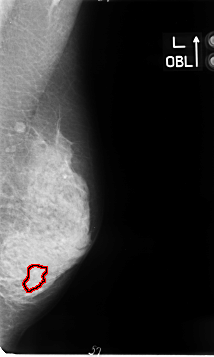

B_3062_1.LEFT_MLO

FILE: B_3062_1.LEFT_MLO.OVERLAY

TOTAL_ABNORMALITIES 1

ABNORMALITY 1

LESION_TYPE MASS SHAPE LOBULATED MARGINS OBSCURED-ILL_DEFINED

ASSESSMENT 3

SUBTLETY 2

PATHOLOGY MALIGNANT

TOTAL_OUTLINES 1

BOUNDARY